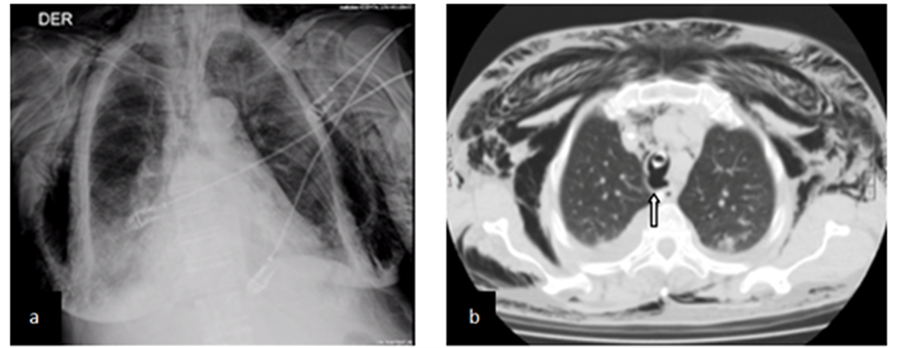

A 77 years old diabetic hypertensive woman with an ancient cerebrovascular occlusive stroke secondary to chronic atrial fibrillation was brought to the Emergency Department with a four day episode of purulent productive cough, fever and dyspnea. Chest X-ray showed consolidation of right lower lobe for which she was started on antibiotics (claritromicine plus ceftriaxone). Two days after, she is on overt respiratory failure (Pa02/Fi0 103) is transferred to the ICU where she needs emergency tracheal intubation guided with stylet and is started on

protective mechanical ventilation. Two hours later she presents progressive anterior chest subcutaneous emphysema which is clearly visible on chest X-ray (Figure 4(a)) and hemodynamic compromise. CT shows pneumomediastinum severe subcutaneous emphysema without associated pneumothorax and an exophitic lesion in the posterior aspect of the trachea, near the distal end of the endotracheal tube (Figure 4(b)). Bronchoscopy two days after this finding depicted a 5 cm longitudinal rupture compromising the medium third of the posterior tracheal wall. The endotracheal tube was repositioned with the cuff distal to the lesion and on the next day, we added instillation of 30 cm3 of activated PRP into the wound through bronchoscope. Antibiotic therapy was changed to imipenem plus vancomycin and the following 4 days the patient evolved favorably, a new CT showed a significant reduction of pneumomediastinum and subcutaneous emphysema with indemnity of the compromised tracheal wall (Figure 4(c)). She was extubated and at the 13th day after the procedure, bronchoscopy showed a firm scar at the site of lesion (Figure 4(d)). One month later the patient is well, without respiratory symptoms and bronchoscopy shows indemnity of the posterior wall of trachea.

Figure 4. (a) Shows X-ray with extense subcutaneous emphysema; (b) Shows CT with exophitic lesion abouting from posterior wall of trachea (arrow); (c) CT scan showing indemnity of posterior wall of trachea at 4th day after procedure; (d) Endoscopy at 13th day after procedure showing scar (arrow).